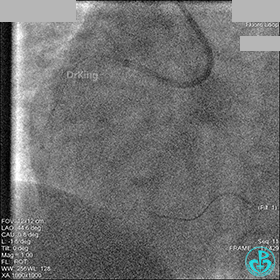

1周后再次上台,右冠脉3级血流,3段局限性严重狭窄,内膜模糊,应该是上次操作夹层遗留下的血肿。

先处理前降支开口严重狭窄并顺利植入前降支到左主干支架。